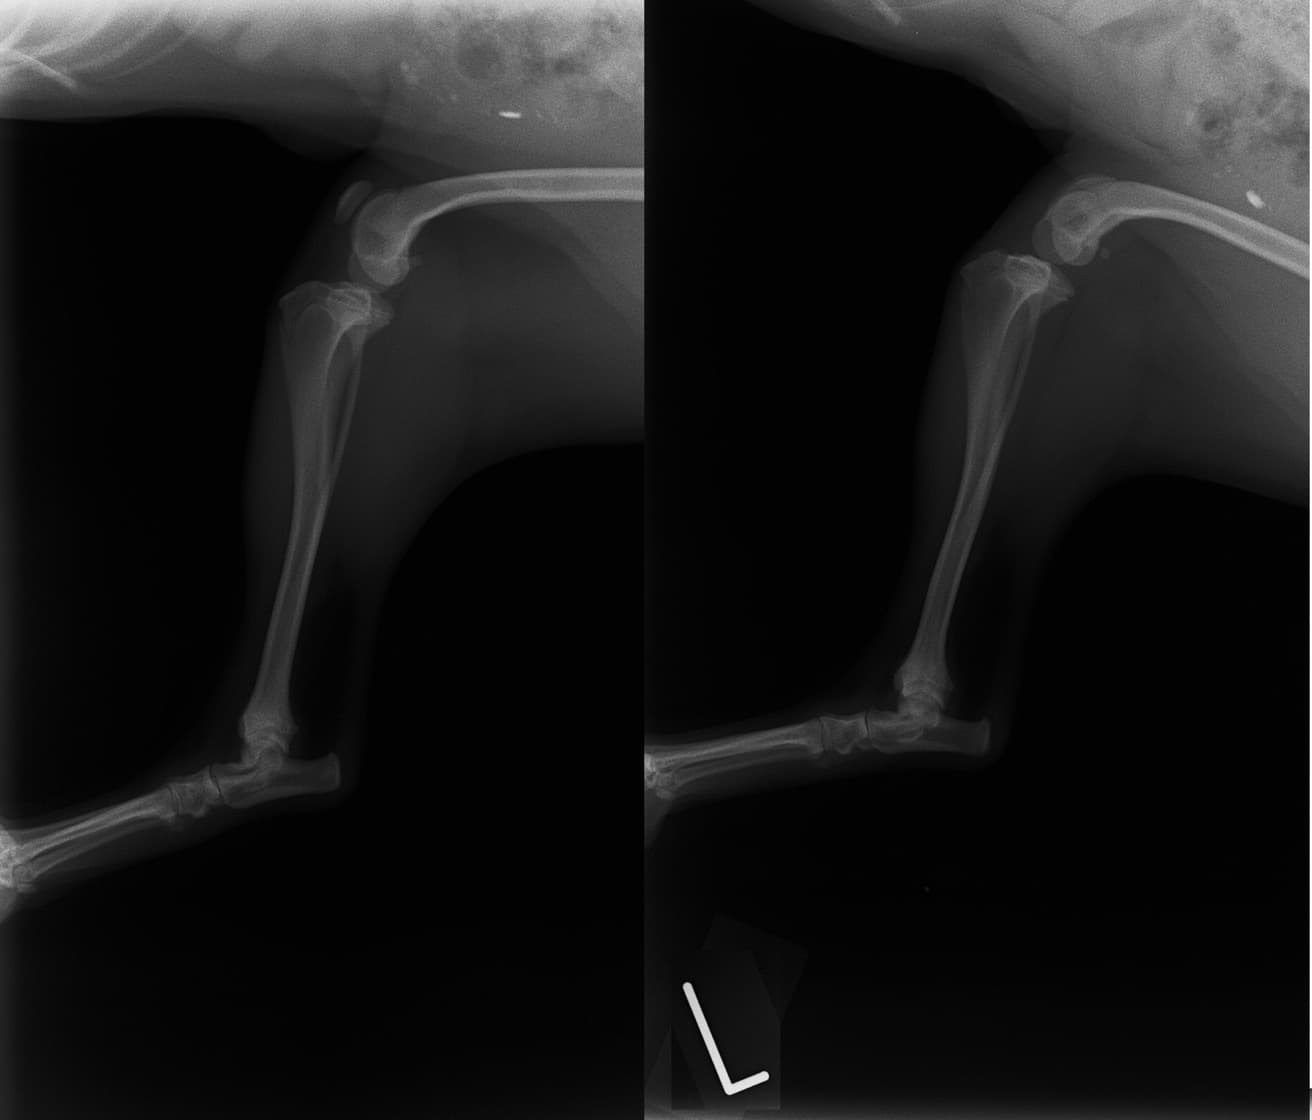

■ 症例20 ポメラニアン 8ヶ月 1.8kg

左右膝蓋骨脱臼 グレードⅢ

2ヶ月前から間欠的跛行が認められ、両膝の膝蓋骨脱臼整復術を行った。

手技は縫工筋及び内側広筋の解放、脛骨粗面の外側転位、滑車ブロック形造溝術、内外側関節包の縫縮を選択し実施した。

右側の膝蓋骨脱臼は上記手技で整復されたものの、左側はそれのみでは膝蓋骨が浮く様子が認められた。その為、PDS縫合糸にて膝蓋靱帯を1糸のみ縫合し、靱帯の縫縮を行った。

膝蓋骨脱臼は膝関節における膝蓋骨の内外側の脱臼と定義されるが、時として単純な内外の脱臼ではなく、膝蓋骨が大きく前方に浮き上がるように脱臼する場合がある。特にトイプードルやポメラニアンといった犬種に多く認められる。

内側脱臼に加えて前方への浮き上がりを矯正する為に、従来より脛骨粗面転移により膝蓋靭帯を外方と下方に引っ張り、固定する方法を選択する。膝蓋骨の前方への浮き上がりが軽度の場合は、従来法ではなく関節包の縫縮で対応していた。しかし、一部の症例で膝蓋骨の動きが悪くなり伸展機構が円滑に機能せずロボット様歩行になるケースがあった。

その為、膝蓋靭帯自体を縫縮する方法を採用した。この方法により、膝関節の伸展機構を妨げず膝蓋骨の軽度の浮きを矯正することが可能となった。

本症例の経過は良好である